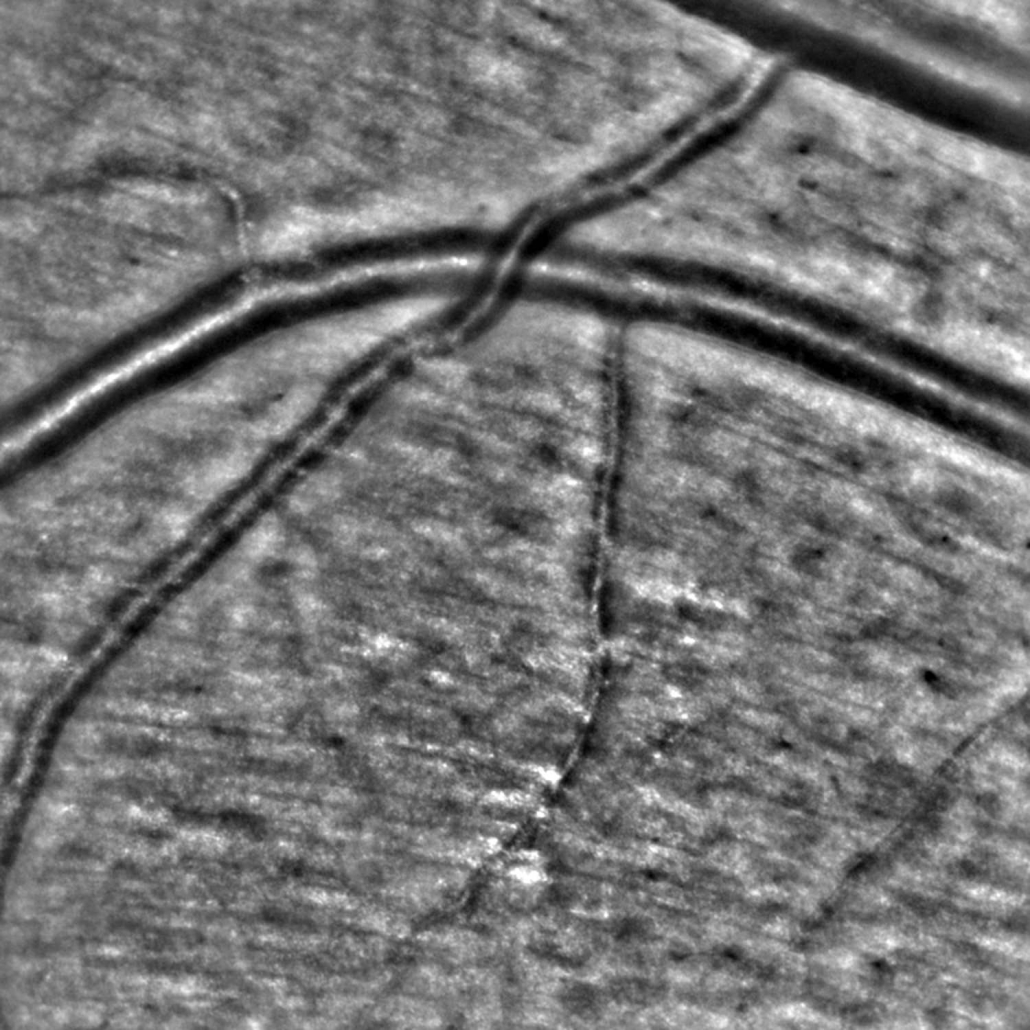

The rtx1 enables visualizing the microscopic walls of retinal arterioles non-invasively, thanks to adaptive optics imaging. Focal narrowing, perivascular sheathing, micro-hemorrhages and micro-aneurisms are also visible without using contrast agents.

AOdetect application also provides supervised image segmentation for analyzing the wall morphology of blood vessels. With this option, rtx1 delivers non-invasive vascular structure metrics with micrometer precision:

The exact same vascular section is assessed on follow-up images with a only a few clicks.